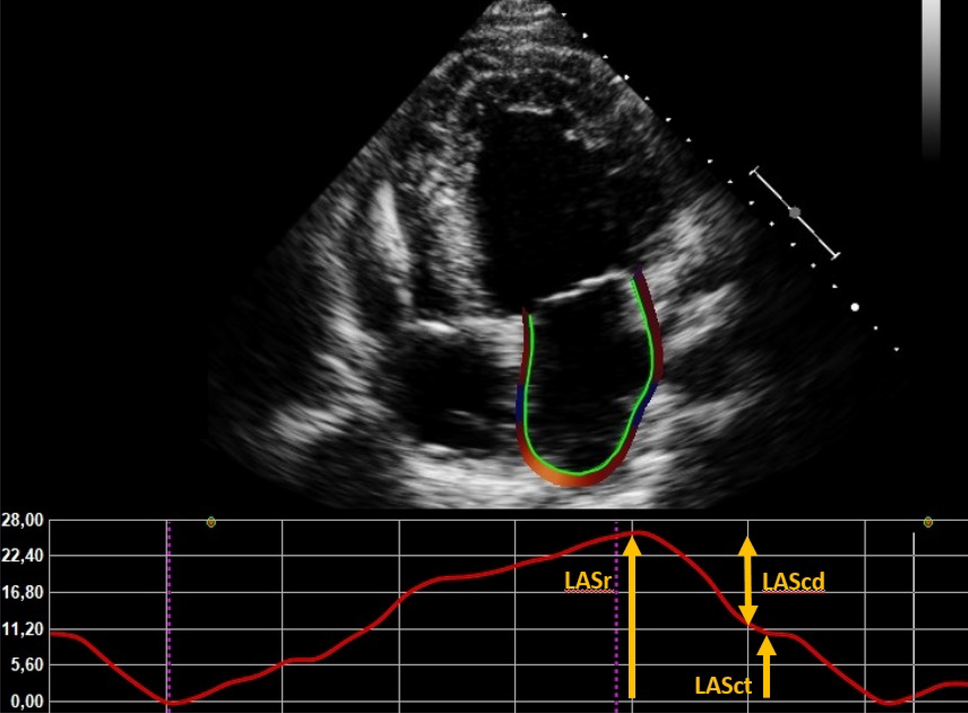

Strain parameters were measured with speckle tracking echocardiography (also using TomTec Imaging Systems) by a single operator, according to the prevailing consensus document of the EACVI/ASE/Industry Task Force to standardize deformation imaging [17]. The apical 4-chamber view was used preferably for the analysis. LA endocardial borders were automatically traced. The LA is contoured extrapolating across the pulmonary veins and LA appendage orifice [19]. We used end-diastole as a reference. Fine-tuning was performed manually if the tracking was suboptimal. If the quality of the 4-chamber view was poor, the 2-chamber view was used. Patients with insufficient image quality to perform LA strain analysis or patients with an atrial pacemaker were excluded. LA strain was assessed according to the three phases of the LA cycle: LA reservoir strain (LASr) which starts at the end of ventricular diastole (mitral valve closure) and continues until mitral valve opening (20). An example of a LA strain curve is provided in Fig. 1. Global longitudinal strain (GLS) was assessed in 18 LV segments on the standard apical four-, three-, and two-chamber views, where the endocardial border was traced manually at end-systole. The mean GLS from the three apical views was considered the LV GLS. If a patient had AF during the echocardiography, the index beat method was used. This is a validated method to measure echocardiographic parameters during AF [21].

Fig. 1

Example of LA strain measurement. LASr left atrial reservoir strain, LAScd left atrial conduit strain, LASct left atrial contractile strain